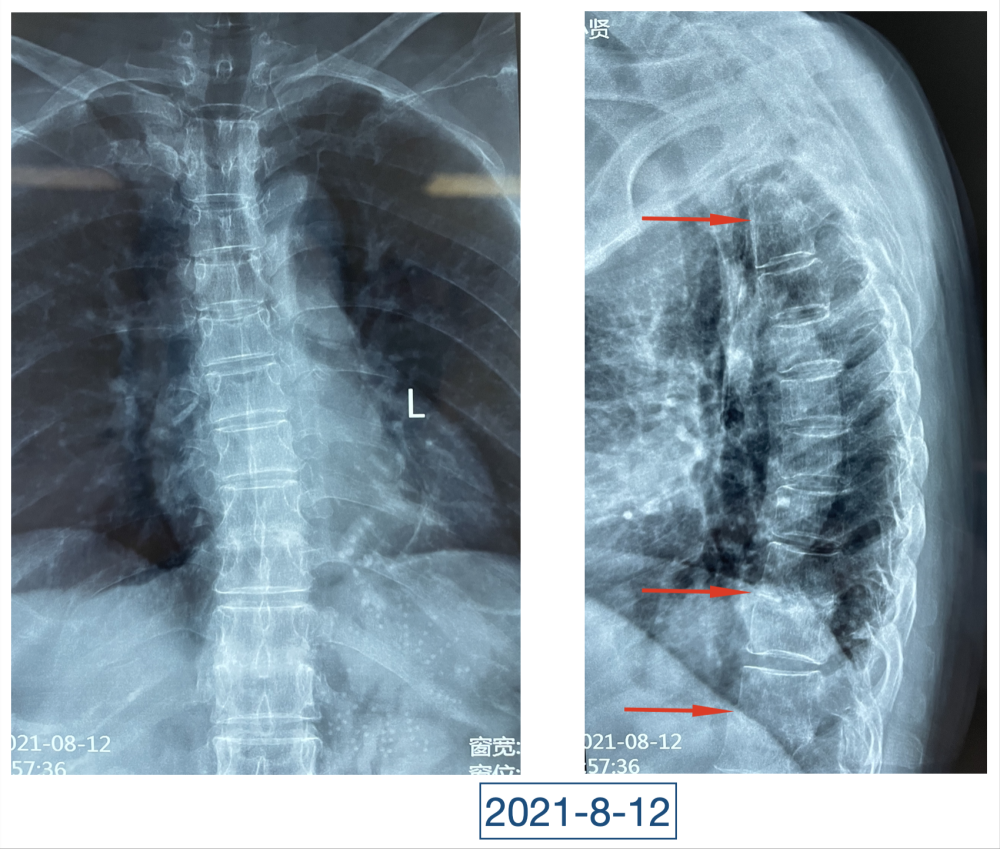

全身上下11处骨关节被破坏!密密麻麻的诊断看得李辉毫无思绪,这么久都查不出来的病因能让他查出来吗?一时间,他也说不出话。看着黄大娘深深凹陷的双眼,浑身上下几乎看不见肉,就像罩着一层饥饿的青黄色的薄皮。过了好一会儿,他叹了口气,说:“先住下吧,用药把关节疼痛缓解一下,再想办法。”

经过科室讨论、会诊,李辉也查阅了很多资料,按照黄大娘的症状,他跟之前的接诊医生一样,觉得应该是骨关节感染。可之前的穿刺、培养各种检查也做过,为什么没有找到致病菌?李辉想,或许是检查中出现了问题,没有查对地方。于是他决定,在B超引导下骨穿刺,通过最新技术精准定位病灶,只有这样也许才能抓到真正的“罪犯”。

在黄大娘入院第四天,李辉将她推入检查室,结果很快出来了,为烟曲霉菌感染。这个结果验证了李辉的想法,也解释了此前抗感染药物为何一直不奏效。“找到元凶就好办了,对症用药就可以。真菌感染本来治疗时间就很长,骨科类感染灶治疗时间更长,用了5个月的时间,终于治好了。”

近日随访得知黄大娘身体好转,李辉脸上的笑容掩饰不住,他说,据查阅文献,11处感染灶,这是全世界感染灶最多的骨关节感染,但现在,这罕见、复杂的病已经被治愈。